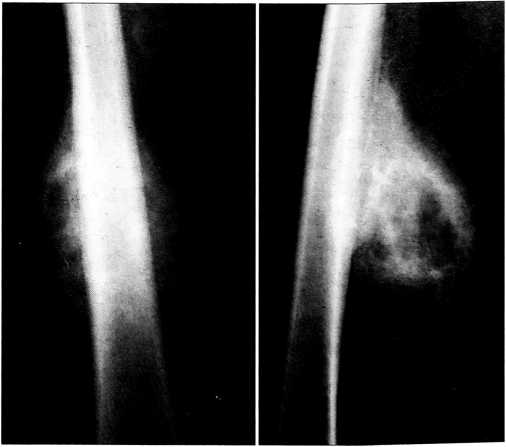

Больная К., 14 лет, больна 5 мес. Указаний на травму нет. Заболевание началось с появления припухлости по задней поверхности правого бедра. На рентгенограммах на уровне диафиза правого бедра выявлено дополнительное пароссальное образование костной плотности овальной формы с нечеткими контурами. В очаге имеются участки остеосклероза и отдельные кисты. Граница между пароссальным образованием и диафизом бедренной кости нечеткая, дифференцируется частично ассимилированный линейный периостит (рис. 3). Выявленные изменения не позволили полностью исключить пароссальную саркому, что усложнило проведение дифференциальной диагностики. Ребенку выполнены одна за другой две открытые биопсии. Верифицировать диагноз не удалось. Через 3 мес от начала заболевания вновь произведена открытая биопсия в НИИ детской онкологии ОНЦ РАМН и диагностирован гетеротопический оссификат.

При поступлении в ЦИТО ходит самостоятельно, хромая на правую ногу. На правом бедре по латеральной поверхности два послеоперационных рубца длиной 11 см, тут же, больше кзади, пальпируется опухолевидное образование размером 17x7 см, не спаянное с кожей и подкожной клетчаткой, безболезненное при пальпации. Кожа над ним не изменена. В правом коленном суставе разгибание 170°, сгибание полное.

Спустя 5 мес от начала заболевания произведена краевая резекция правой бедренной кости с включением в препарат оссификата. Иммобилизация кокситной гипсовой повязкой продолжалась 3 нед. При перевязках в мягкие ткани зоны разреза дважды вводился гидрокортизон в дозе 50 мг. Заживление раны первичное. Ходьба на костылях без нагрузки на больную ногу в течение 3 мес.

Рис. 3. Рентгенограммы больной К. Гетеротопический оссификат правого бедра (дифференциальная диагностика с пароссальной саркомой). Нечеткий контур оссификата, структура с участками остеосклероза и разрежения. Частично ассимилированный линейный периостит бедренной кости.

Морфологическое исследование операционного препарата: определяется относительно зрелая губчатая кость с нарушенной архитектоникой, о чем свидетельствует неравномерное распределение и созревание костных балочек. Элементов остеоидной и грубоволокнистой кости не обнаружено.